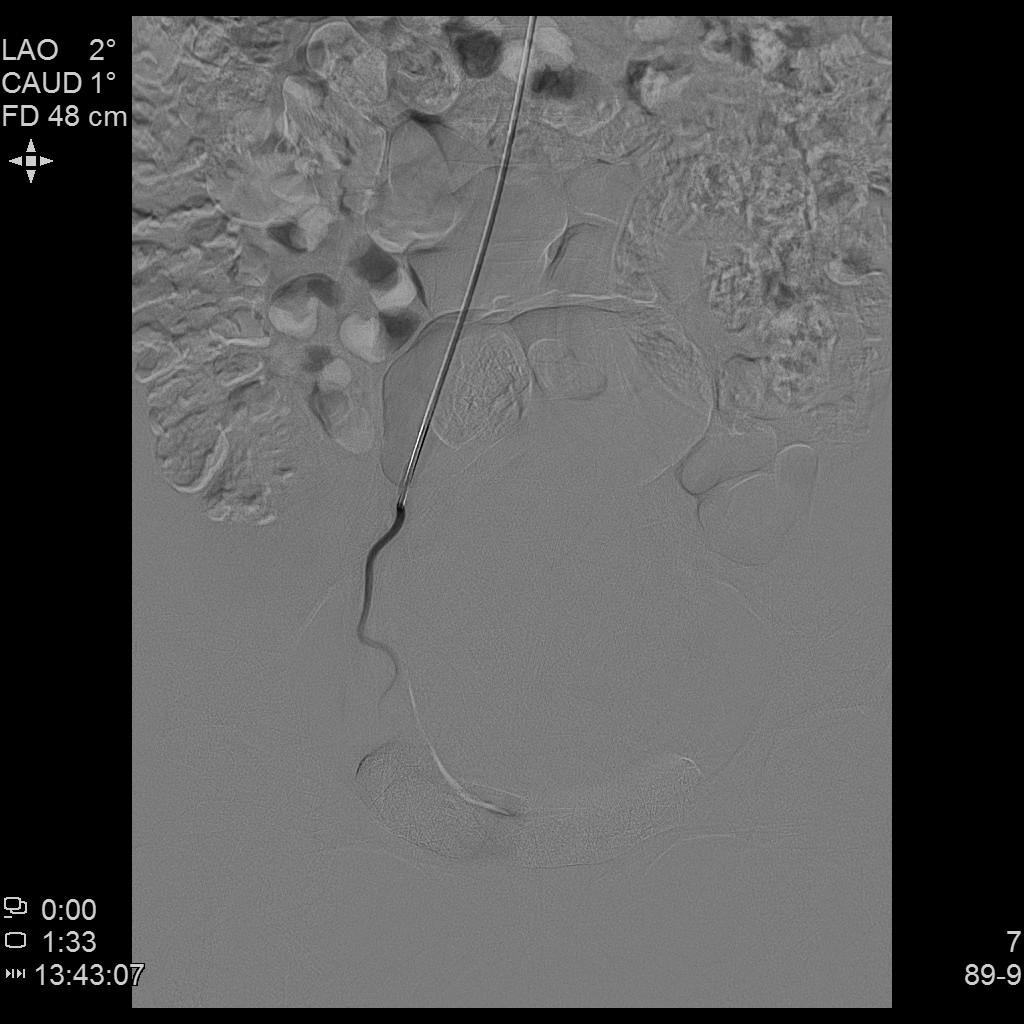

例3

中年患者,发现“子宫腺肌症”10年余,近5年痛经、月经量增多等症状明显加重,导致贫血,严重影响生活质量。

- 术前彩超、磁共振检查显示子宫明显增大,子宫前壁可见弥漫型子宫腺肌症病灶,合并粘膜下、肌壁间子宫肌瘤。

右侧子宫动脉造影

- 术后患者痛经、月经量过多症状迅速缓解,生活质量明显改善。